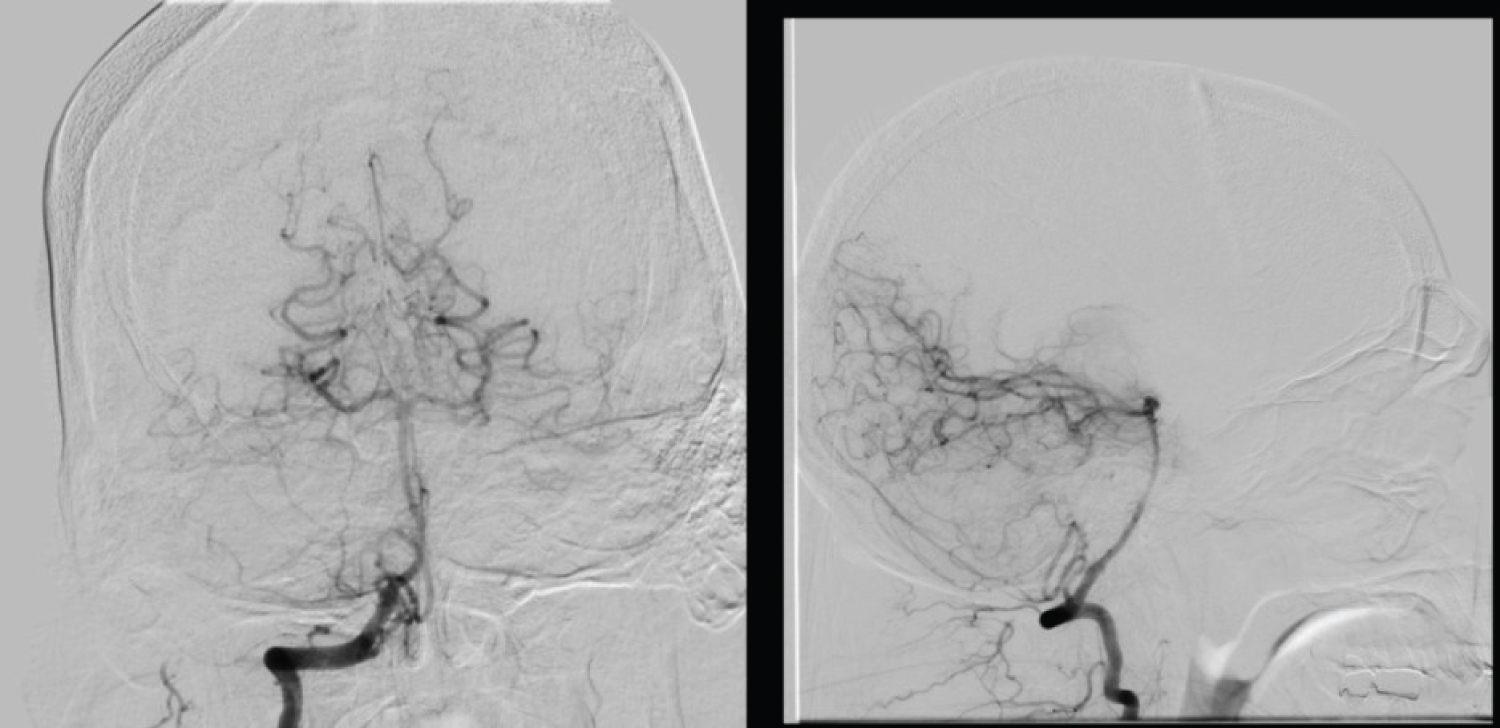

Given the patient’s obstructive hydrocephalus and 4.9 cm hemorrhage, he was transferred to the intensive care unit (ICU) for close monitoring for possible ventriculostomy and suboccipital craniotomy. The Hemovac drain was removed to decrease the possibility of CSF egress worsening his cerebellar hemorrhage. His systolic blood pressure was kept strictly below 140 mmHg and hypertonic saline was administered as needed to reduce cerebral edema. He remained in the ICU for 11 days with serial head CT imaging showing improvement of his cerebellar hemorrhage and hydrocephalus (Figure 2). Midway through the clinical course, a 6-vessel digital subtraction angiography was performed and ruled out the presence of an aneurysm, dural venous sinus thrombosis, or arteriovenous malformation (AVM), which could have significantly altered the management approach (Figure 3). The patient’s mental status rapidly improved during his ICU course and remained stable. Throughout his hospitalization, extensive discussions were held on whether the patient was a suitable candidate for surgery or ventriculostomy given his neurological exam. Ultimately, the decision was made against surgery given his rapid improvement and ongoing stability.

Figure 3: 6-vessel digital subtraction angiography ruling out the presence of an aneurysm or arteriovenous malformation. View Figure 3